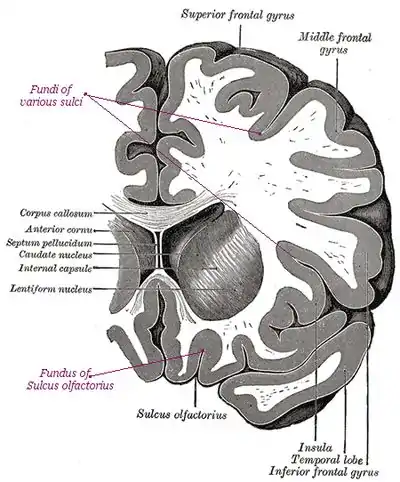

Fundi, sulci, and gyri in a section across a human brain

The deepest part of a sulcus, such as the sulci in the human cerebral cortex.